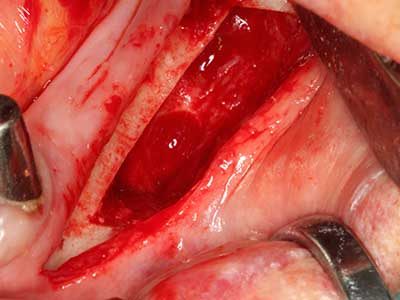

Si es preciso realizar intervenciones quirúrgicas en las que el hueso está en contacto directo con estructuras sensibles, como son los vasos sanguíneos o los nervios, los instrumentos rotativos presentan un enorme potencial de provocar lesiones iatrogénicas. Así, precisamente en la representación de nervios después de una lesión iatrogénica, o en el transcurso de la lateralización de un nervio para resecciones, reconstrucciones o incorporación de implantes, los equipos piezoeléctricos pueden resultar muy útiles para preparar la tapa ósea y retirar las partes de tejido duro cercanas al nervio (fig. 17-20). Por lo general, un ligero contacto del cordón nervioso con el inserto piezoeléctrico no tiene consecuencia alguna; ahora bien, un procedimiento poco cuidadoso con movimientos tipo sierra o piezas de trabajo sobre la base ósea aún existente puede provocar lesiones nerviosas temporales o incluso permanentes. Con todo, el riesgo de sufrir una lesión de este tipo se considera significativamente inferior que en los casos en los que se utilizan sierras y fresas (Pereira, Gealh et al. 2014).

Fig. 17: Tomografía computarizada de un osteoma de crecimiento progresivo ...

Fig. 17b: justo al lado del canal alveolar con irritación nerviosa (vista lateral y coronal).

Fig. 18: Preparación de una tapa cortical con la sierra ósea piezoeléctrica (Piezomed, W&H).

Fig. 19: Zona operada después de neurolisis y eliminación del osteomo.